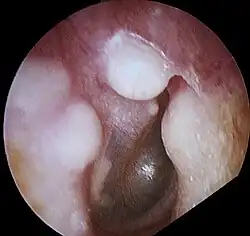

Osteoma of external auditory meatus

An osteoma (plural osteomas or less commonly osteomata) is a new piece of bone usually growing as a benign tumour on another piece of bone, typically the skull. When grown on other bone it is known as "homoplastic osteoma"; on other tissue it is called "heteroplastic osteoma".[1]